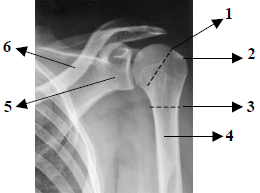

Observe atentamente a imagem radiográfica abaixo e em seguida responda à questão.

Assinale a alternativa que apresenta, em ordem numérica crescente, as estruturas assinaladas na imagem radiográfica anteriormente apresentada.